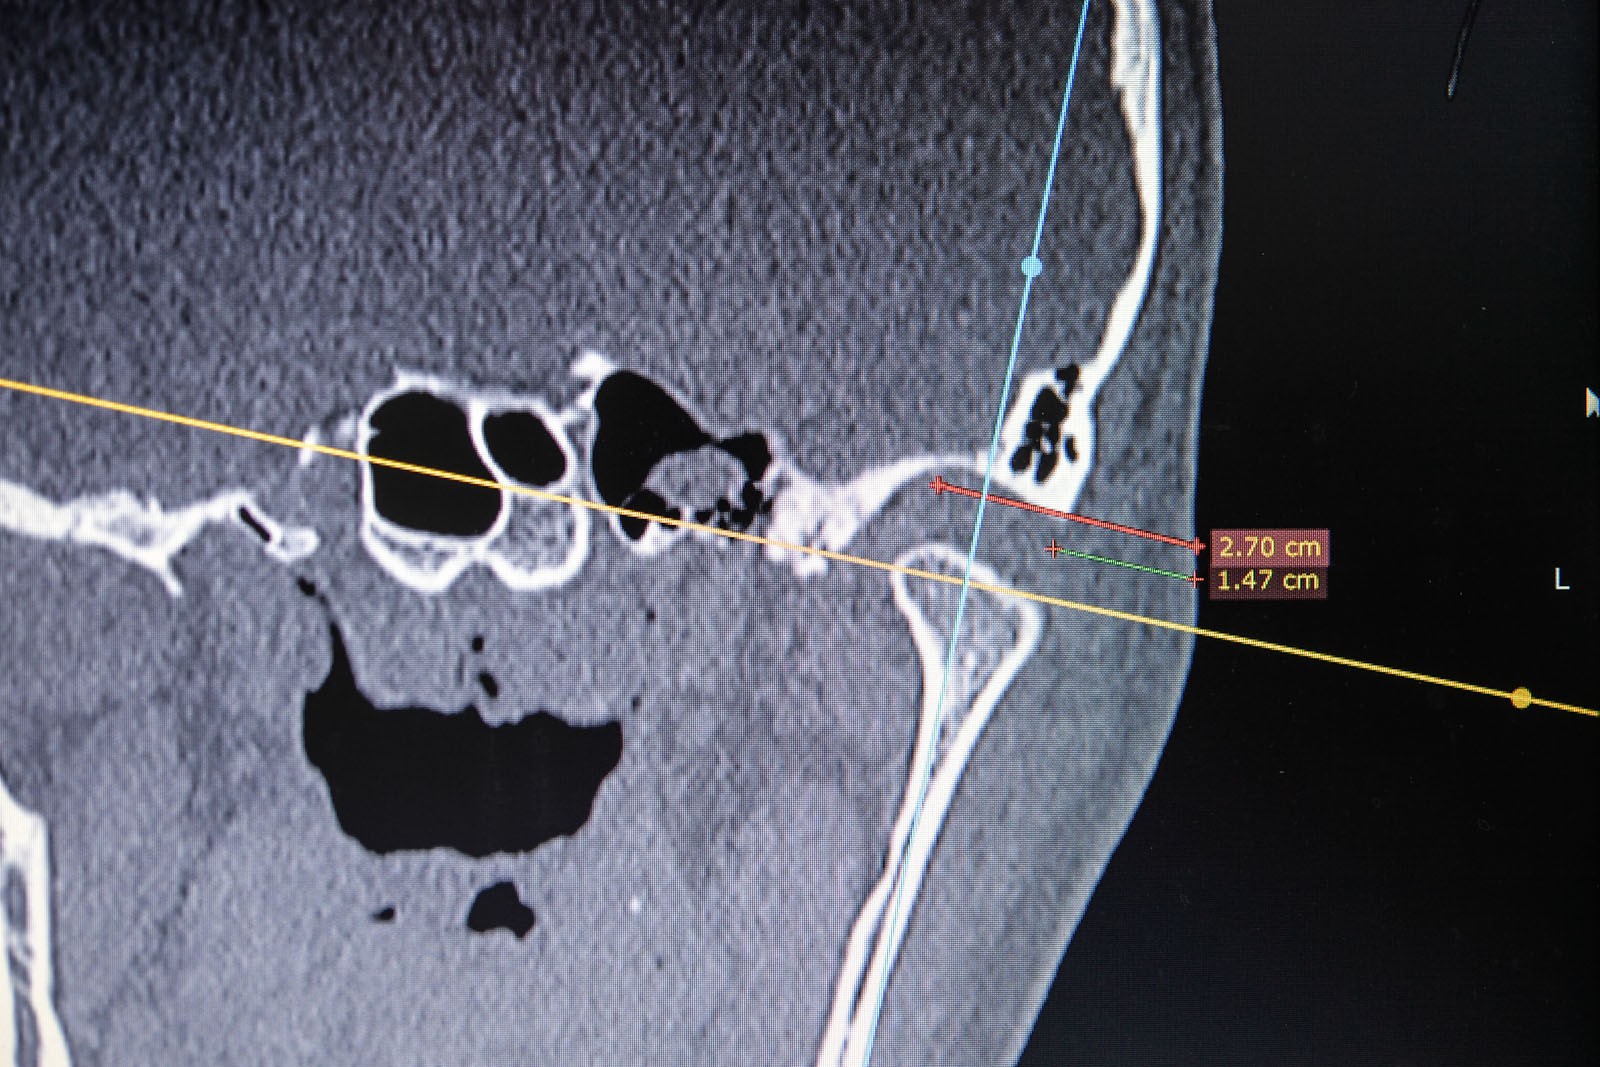

Metoda Gerbera jako punkt wyjścia dla analizy traktuje staw skroniowo-żuchwowy. W relacji do jego funkcji bierze pod uwagę pozostałe ogniwa układu stomatognatycznego. Staw skroniowo-żuchwowy jest działającym synchronicznie symetrycznym elementem anatomii twarzoczaszki, który pozwala na otwieranie ust i funkcje z tym związane. To staw o złożonej budowie, w jego skład wchodzą: dołek stawowy kości skroniowej, który stanowi panewkę stawową, wyrostek kłykciowy, krążek stawowy i torebka stawowa. Krążek zbudowany jest z chrząstki i dzieli jamę stawową na dwie części: górną i dolną. Podczas ruchów opuszczania żuchwy (otwierania ust) krążek stawowy przesuwa się do przodu i dołu. Wraz z krążkiem przesuwa się wyrostek kłykciowy głowy żuchwy po obu stronach. W ruchu przywodzenia żuchwy (zamykania ust) krążek stawowy i wyrostek kłykciowy żuchwy wracają na swoje miejsce do pozycji wyjściowej. Stawy są sprzężone ze sobą czynnościowo (ruch następuje równocześnie w obu stawach) i anatomicznie (łączy je trzon kości żuchwy), stąd też nieprawidłowe asymetryczne obciążenia stawów są najczęstszą z przyczyn zaburzeń narządu żucia.

W ocenie wewnątrzstawowych patologii pomocna jest diagnostyka obrazowa. Konwencjonalne zdjęcia radiologiczne OPG, tomografia komputerowa oraz stożkowa tomografia komputerowa CBCT pozwalają na ocenę elementów kostnych stawu skroniowo-żuchwowego. Ocenę tkanek miękkich zlokalizowanych wewnątrzstawowo umożliwia rezonans magnetyczny NMR.

W pierwszym etapie wykonuje się modele robocze, które są montowane w opracowanym przez prof. Gerbera artykulatorze. Tak zwany condylator pozwala na symulację trójwymiarowych ruchów głów żuchwy. Pozwala na zweryfikowanie poprawności relacji pomiędzy łukiem zębowym górnym a dolnym. Po dokładnym zbadaniu funkcji i morfologii stawu sż, wykonaniu pomiarów oraz ocenie stanu zdrowia zębów zostaje opracowany indywidualny plan leczenia zgodny z uwarunkowaniami pacjenta.

Dzięki zastosowaniu łuku twarzowego możliwy jest pomiar kątów nachylenia torów przesuwania głów żuchwy. Pozwala to na zamontowanie modeli gipsowych w stosunku do stawów skroniowo-żuchwowych i płaszczyzny Campera (linii uszno-nosowej) orientacyjnej w widoku z profilu. Ma to na celu odtworzenie prawidłowej okluzji, czyli odpowiedniej pozycji stykania się zębów górnych z dolnymi.